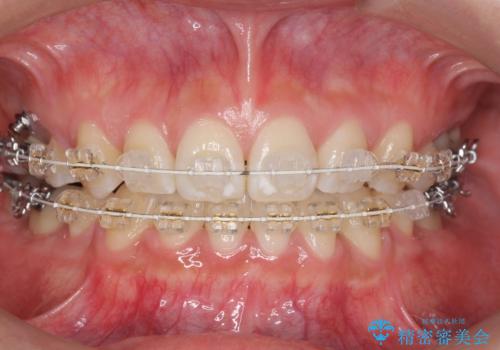

真ん中が右にずれている 前歯のがたつき 治療途中に地方へ引っ越したが、通ってワイヤー矯正

- 前歯のがたつきを主訴に来院。

前歯のクロスバイト、上の前歯の正中が右にずれていました。

右上の奥歯の高さもない状態でしたが、矯正治療が終わってからしっかりかぶせました。

上下左右の小臼歯を抜歯しています。